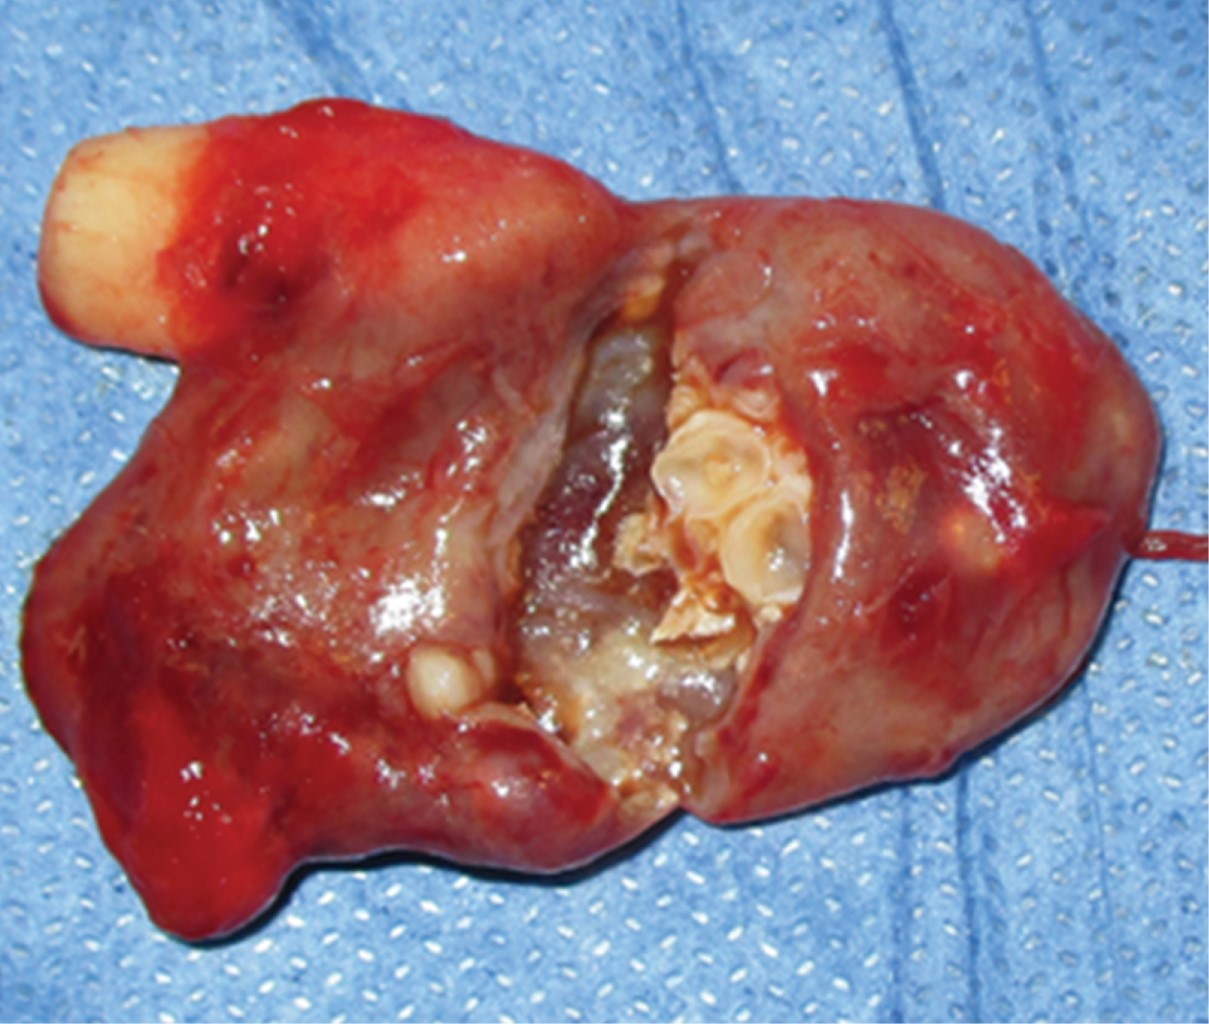

Calcifying odontogenic cyst associated with compound odontoma. Clinical case report and literature review

The calcifying odontogenic cyst is a rare pathological entity of the jaws, described for the first time by Gorlin in 1962 as a benign neoplasm that represents between 0.37-2.1% of all odontogenic tumors. It is found within the lesions that develop ghost cells, which has generated much controversy regarding its classification, management and prognosis. Its simultaneous presentation with other pathological entities is extraordinarily atypical, with scarce literature reporting this association. We present the clinical case of a male patient of 12 years of age with definitive histopathological diagnosis of calcifying odontogenic cyst associated to odontoma composed with its surgical management as well as a review of the literature.

Figure 1

Figure 2

Figure 3

Figure 4

Figure 5

Figure 6